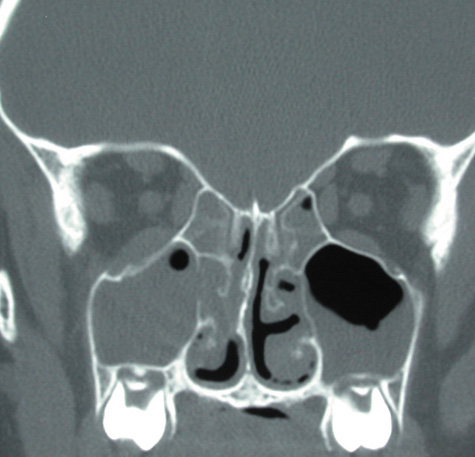

CT should be performed using thin-section (2–4 mm) high-resolution scanning with multiple views of both bone and soft tissue detail.53 Axial and coronal views should be obtained; in one-third of patients with subperiosteal abscesses, the abscess was seen in the coronal sections only.18 Helical CT is a fairly new technology that allows increased resolution with decreased imaging time.60 This type of scan may be especially beneficial in children because of the ability to obtain good imaging with a shorter imaging time.60 elica He HhIntravenous contrast material is not advocated at all centers because there is intrinsically high contrast between infectious changes and orbital fat. However, some authors believe that it is essential to the diagnosis, and it thus remains the preference of the individual clinician, as well as the neuroradiologist.22,59,62

With preseptal inflammation, CT demonstrates soft tissue swelling of the eyelids and tissue adjacent to the orbital septum (Fig. 15). The orbit is not involved, and usually the sinuses do not show evidence of inflammation. The distinction between inflammatory preseptal cellulitis and edema cannot be made.63

Fig. 15. Computed tomography showing preseptal cellulitis of left eye. Note that all swelling is anterior to the orbital septum.